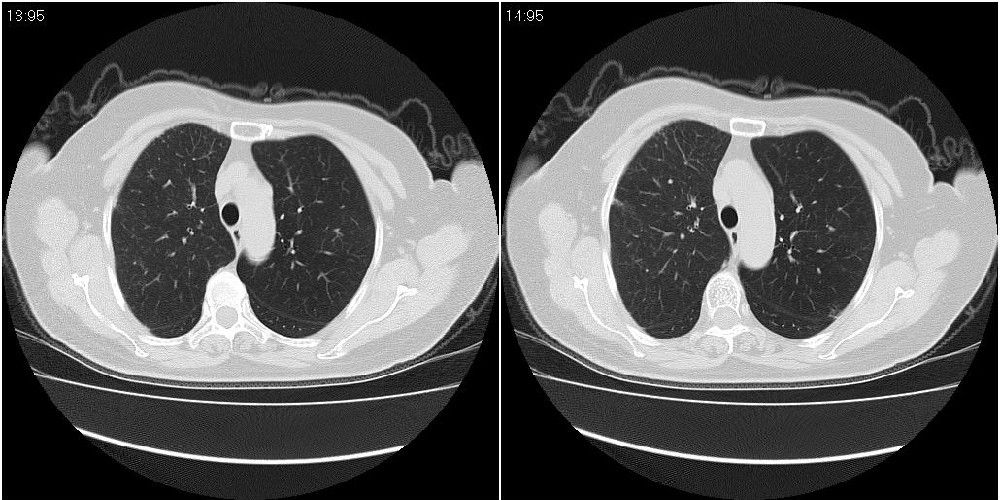

女性,72岁。去年9月份发现肺部病变,诊为肺结核并进行正规治疗至今,但复查后发现ct表现几乎没有变化。

右侧中叶支气管明显狭窄,建议行纤支镜检查!

右中间段支气管局限性狭窄,右中叶支气管亦稍显狭窄,但并未见明显占位表现,半年多了,无变化也许是好事,可能为炎性狭窄,建议继续随访。

双肺继发型tb并右中叶内膜tb,轻度支扩,左下胸膜肥厚粘连。

右中叶炎性改变,支气管狭窄但较光滑,占位可能性不大。

右中间段支气管局限性狭窄,右中叶支气管亦稍显狭窄.

双肺继发性肺结核并右肺中叶节段性肺不张,左下胸膜肥厚粘连。

右肺中叶节段性肺不张,考虑结核或慢性炎症,建议做纤支镜检查。

双肺继发性肺结核并右肺中叶节段性肺不张